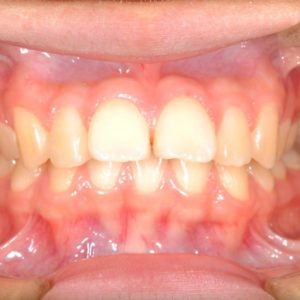

虫歯の治療、矯正の相談をご希望され来院されました。お口の中を診査(レントゲン写真、口腔内写真、視診)させていただいたところ、虫歯については問題なくきれいに歯磨きされているようでした。 正面から見るとジグザグしており、お口 […]

全体的な歯並びの矯正治療を行いました。治療期間は3年間。

ジグザグの歯並びを気にされてご来院されました。. 見た目の問題も大切ですが、それ以上に清掃がしにくいために虫歯・歯周病に非常になりやすく、不正咬合(良くないかみ合わせ)は顎の関節に負担をかけてしまい顎関節症を引き起こす可 […]

歯の大きさに対する顎の大きさのスペース不足により歯が並びきらず、ジグザグの歯並びおよび上の前歯が出っ歯になっていました。 左右4番の歯を抜歯することにより歯を並べるスペースを確保し、歯並びを揃えました。 全体の歯並びが綺 […]